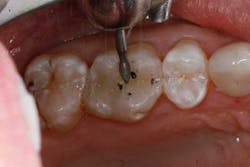

The tooth was prepared and a total etch technique utilizing 37% phosphoric acid was performed (Figs. 3 through 5). After the etchant was rinsed, a desensitizer was placed and blotted to leave a moist dentin surface for bonding (Fig. 6). The bonding agent was applied; the ethanol solvent was air evaporated using a warm air dryer; and the adhesive light-cured for 10 seconds (Figs. 7 and 8).